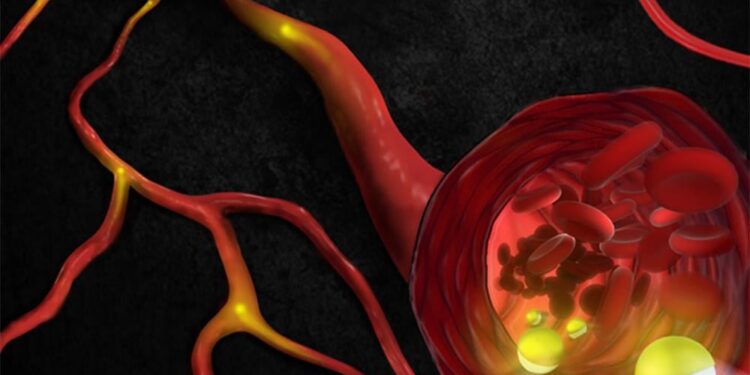

Macrofagen spelen een cruciale rol in het immuunsysteem door ziektekiemen, apoptotische cellen en vreemd materiaal te consumeren en weefselregeneratie te bevorderen. Door elektrische stimulatie toe te passen op deze cellen, kunnen onderzoekers hun gedrag veranderen op een manier die ontstekingen onderdrukt en de genezing versnelt. Dit kan leiden tot een snellere en effectievere genezing van zowel ziekten als verwondingen.

De ontdekking is gebaseerd op onderzoek naar menselijke macrofagen geïsoleerd uit gezond donorbloed. Door de cellen bloot te stellen aan elektrische stromen, konden de onderzoekers veranderingen in de cellen waarnemen die wijzen op een ontstekingsremmende toestand en een bevordering van weefselherstel. Elektrische stimulatie bleek de expressie van genen te verhogen die de ontwikkeling van nieuwe bloedvaten bevorderen, wat essentieel is voor weefselregeneratie.